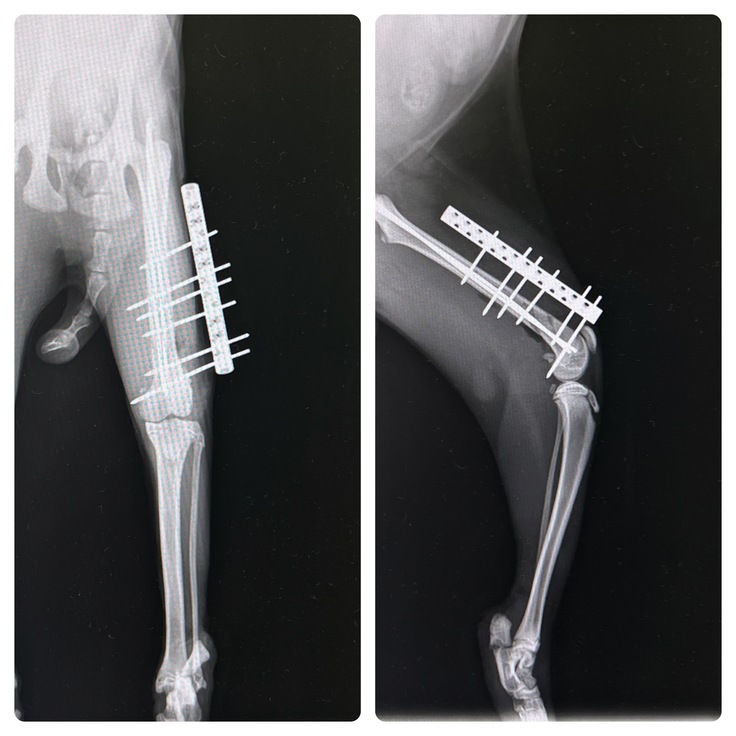

⑤10月7日 手術当日

骨折した骨を支えるボルトを入れる手術の日。

思ったより手術は長引いたようで『手術は無事におわりました』と電話がきたのは夜でした。

開けてみないとわからないが骨の状態が良ければ中に支柱を入れるだけの手術の予定でした。

その場合は通院も少なく済み、再手術もいらないので一番いいと話しておりましたが、

開けてみると骨はレントゲンには映らないような細かなヒビが入っていたため、外からも固定が必要になり、

消毒など術後に定期的な通院と骨が完治してからまた摘出のために麻酔をかけた状態の手術が必要な外側固定もついたと言われました。

▲術後の左大腿骨のレントゲン写真

外側固定をつけなければならなかったことは残念ではありましたが、それだけ大きな事故に遭っていた事実と、今日までとても痛かっただろうということを思い、胸が痛みました。

でもこれでやっと痛みが少しでもなくなったなら、元気に歩けるようになるかもという期待も膨らみました。

踵については、とても薄い骨の骨折なので固定は難しく、可動域もある部位のため、外からのしっかりとしたテーピングによる固定で完治を目指すことになりました。